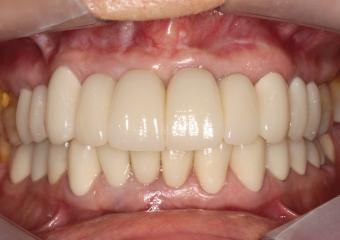

Foto intra oral final 2019

Foto intra oral frontal final 2019